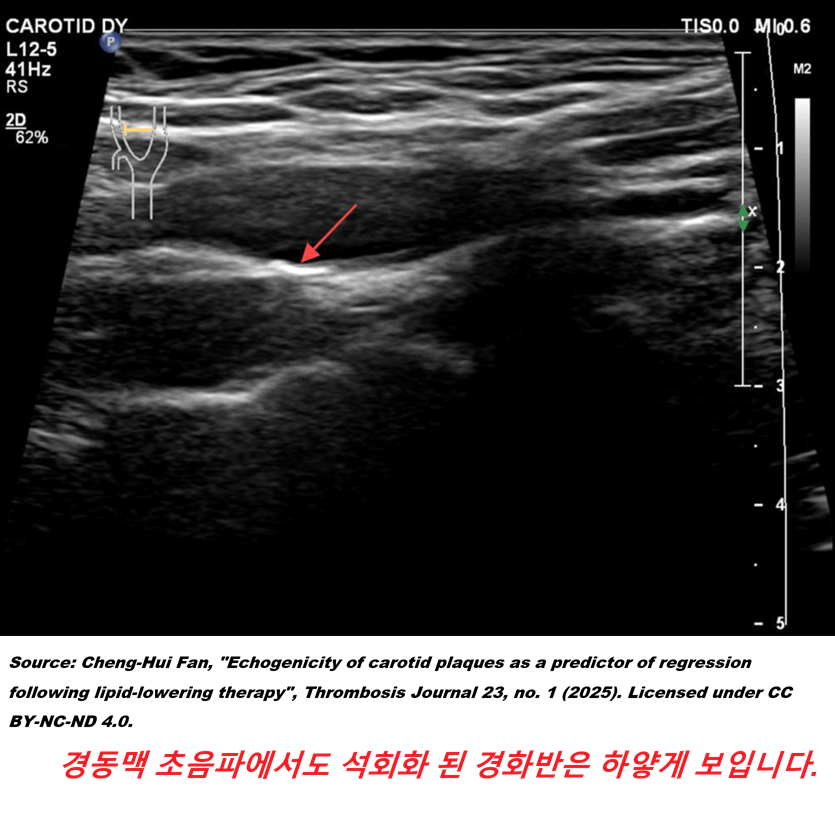

5. 그런데 일반 CT로는 혈관을 볼 수도 없다는데 과연 뭘 보려고 검사를 권유하는 걸까요? 그 해답은 바로 오늘의 주제, 석회화 지수(CAC, coronary artery calcium)라 할 수 있습니다. 칼슘이 많은 조직은 CT 검사에서 하얗게 보인다는 점을 이용해 심장 CT 단면에서 하얗게 보이는 부위의 넓이(mm²)를 측정하고, 하얗게 보이는 정도를 하운스필드 단위(HU)라는 단위로 측정 가중치를 주어 점수로 구합니다. (프로그램으로 자동화되어 있음)

carotid_calcifi.png